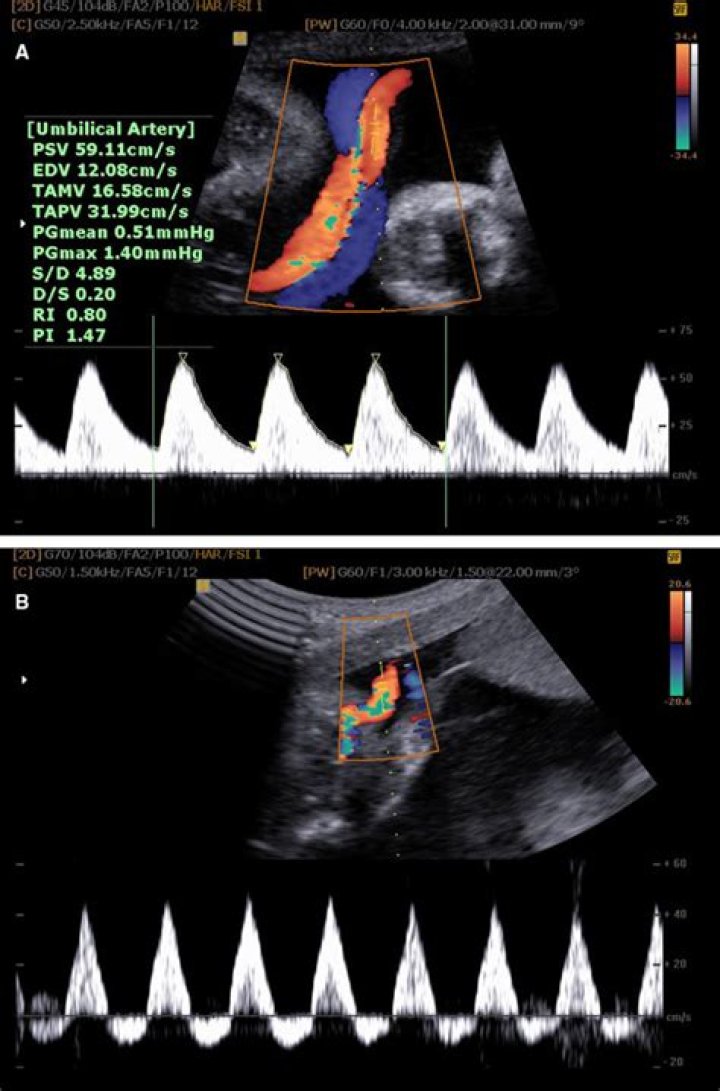

What is normal PI for umbilical artery?

Considering total 2nd and 3rd trimesters the mean PI value of umbilical artery was 1.24 (SD +/- 0.27). While considering the gestational in separate trimesters, study showed that the value of PI in 2nd trimester was 1.33 (SD +/- 0.29) and in 3rd trimester PI was 1.18 (SD +/- 0.25).

What is Ri ratio in pregnancy?

Resistive index ( RI ) = Peak systolic velocity − End diastolic velocity Peak systolic velocity. Systolic : diastolic ratio ( S : D ratio ) = Peak systolic velocity End diastolic velocity.

What is a normal SD ratio?

The systolic/diastolic (S/D) ratio of flow velocities was measured as an index of peripheral resistance. In normal pregnancy the umbilical artery velocity wave S/D ratio declined from 3.9 to 2.1 during the 20th to 40th week while the uterine artery S/D ratio remained constant between 1.8 to 1.9.